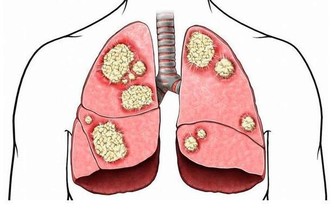

嚴重缺硒則導致免疫力低下、視力減退、易患心血管疾病和腫瘤。

硒有一定的解毒作用,能和體內重金屬結合,減少它們的危害。

建議:含硒食物,最好的是貝類海鮮等,其硒含量比較穩定。